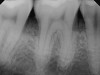

Fig 2. Periapical radiograph showing presence of distal bone loss and calculus.

Figure 2